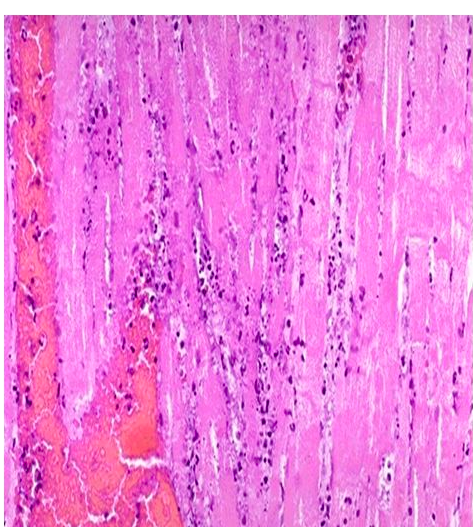

When would this histopatholigcal slide from an MI likely to have occurred

Less than 1 day

Less than 7 days

1-3 week

3-6 weeks